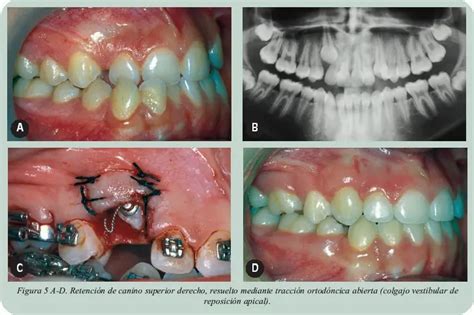

El día de la intervención, el cirujano abre una pequeña ventana en la encía y retira tanto el hueso como la mucosa que obstaculizan la salida de la pieza dental. De esta manera, expone la corona del diente. Unos días después, el ortodoncista coloca un botón en el diente recientemente descubierto. En algunas ocasiones, se puede cementar el botón el mismo día de la cirugía.

Entonces se prepara la corona de dicho diente para cementar un aditamento (bracket o botón) con una ligadura o cadenita de oro y así poder engancharlo al arco. Esto permite aplicar fuerzas controladas para guiar al diente a su posición adecuada en la arcada dental.

Tracción ortodóncica de canino retenido.